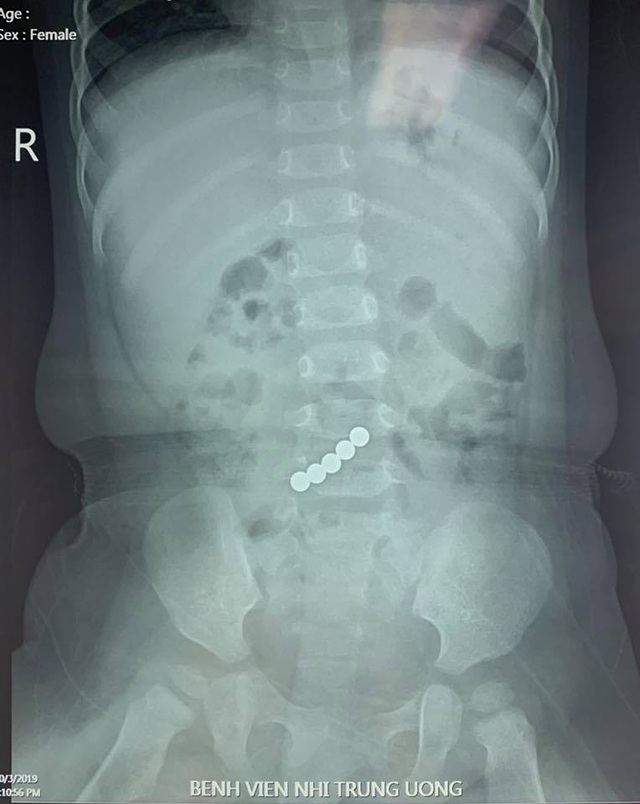

Các nam châm công suất lớn (mạnh gấp 10 đến 30 lần so với nam châm thông thường) được sử dụng trong loại sản phẩm này có nguồn gốc từ kim loại đất hiếm và bắt đầu xuất hiện trong đồ chơi trẻ em cũng như các sản phẩm dành cho người lớn như đồ chơi để bàn vào khoảng đầu những năm 2000. Tất nhiên, bất kỳ đồ vật nhỏ nào cũng có thể tiềm ẩn nguy hiểm đối với trẻ em, bởi chúng có xu hướng đưa các đồ vật vào miệng và có thể nuốt hoặc mắc nghẹn. Nhưng vấn đề là khi nuốt phải nhiều nam châm (hoặc nam châm và một mảnh kim loại khác), lực kéo mạnh giữa chúng có thể làm hỏng hoặc gây ra các vật cản bên trong ruột. Trong trường hợp xấu nhất, nạn nhân sẽ tử vong hoặc cần được phẫu thuật khẩn cấp để cắt bỏ các phần ruột của họ.

Nhưng khi loại nam châm này quay trở lại, các báo cáo đã tăng vọt. Trong năm 2018 và 2019, số lượng báo cáo trung bình mỗi năm tăng 444% so với thời kỳ nam châm bị cấm. Số cuộc gọi yêu cầu sự chăm sóc y tế nghiêm túc, chẳng hạn như nhập viện, cũng tăng 355%. Hơn nữa, 39% tất cả các cuộc gọi báo cáo vấn đề liên quan đến nam châm trong nghiên cứu chỉ xảy ra trong hai năm đó.

Chẳng hạn, một nghiên cứu được công bố vào tháng 12/2020 cho thấy tỷ lệ trẻ em đến khám bệnh liên quan đến nam châm đã tăng 82% từ năm 2017 đến năm 2019, so với các năm từ 2013 đến 2016. Một nghiên cứu khác vào năm 2017 cho thấy ít nhất 15.000 trẻ em ở Mỹ đã đến phòng khám điều trị từ năm 2010 đến năm 2015 với các chấn thương liên quan đến nam châm, nhưng các trường hợp bắt đầu giảm sau các hành động của CSPC vào năm 2012.